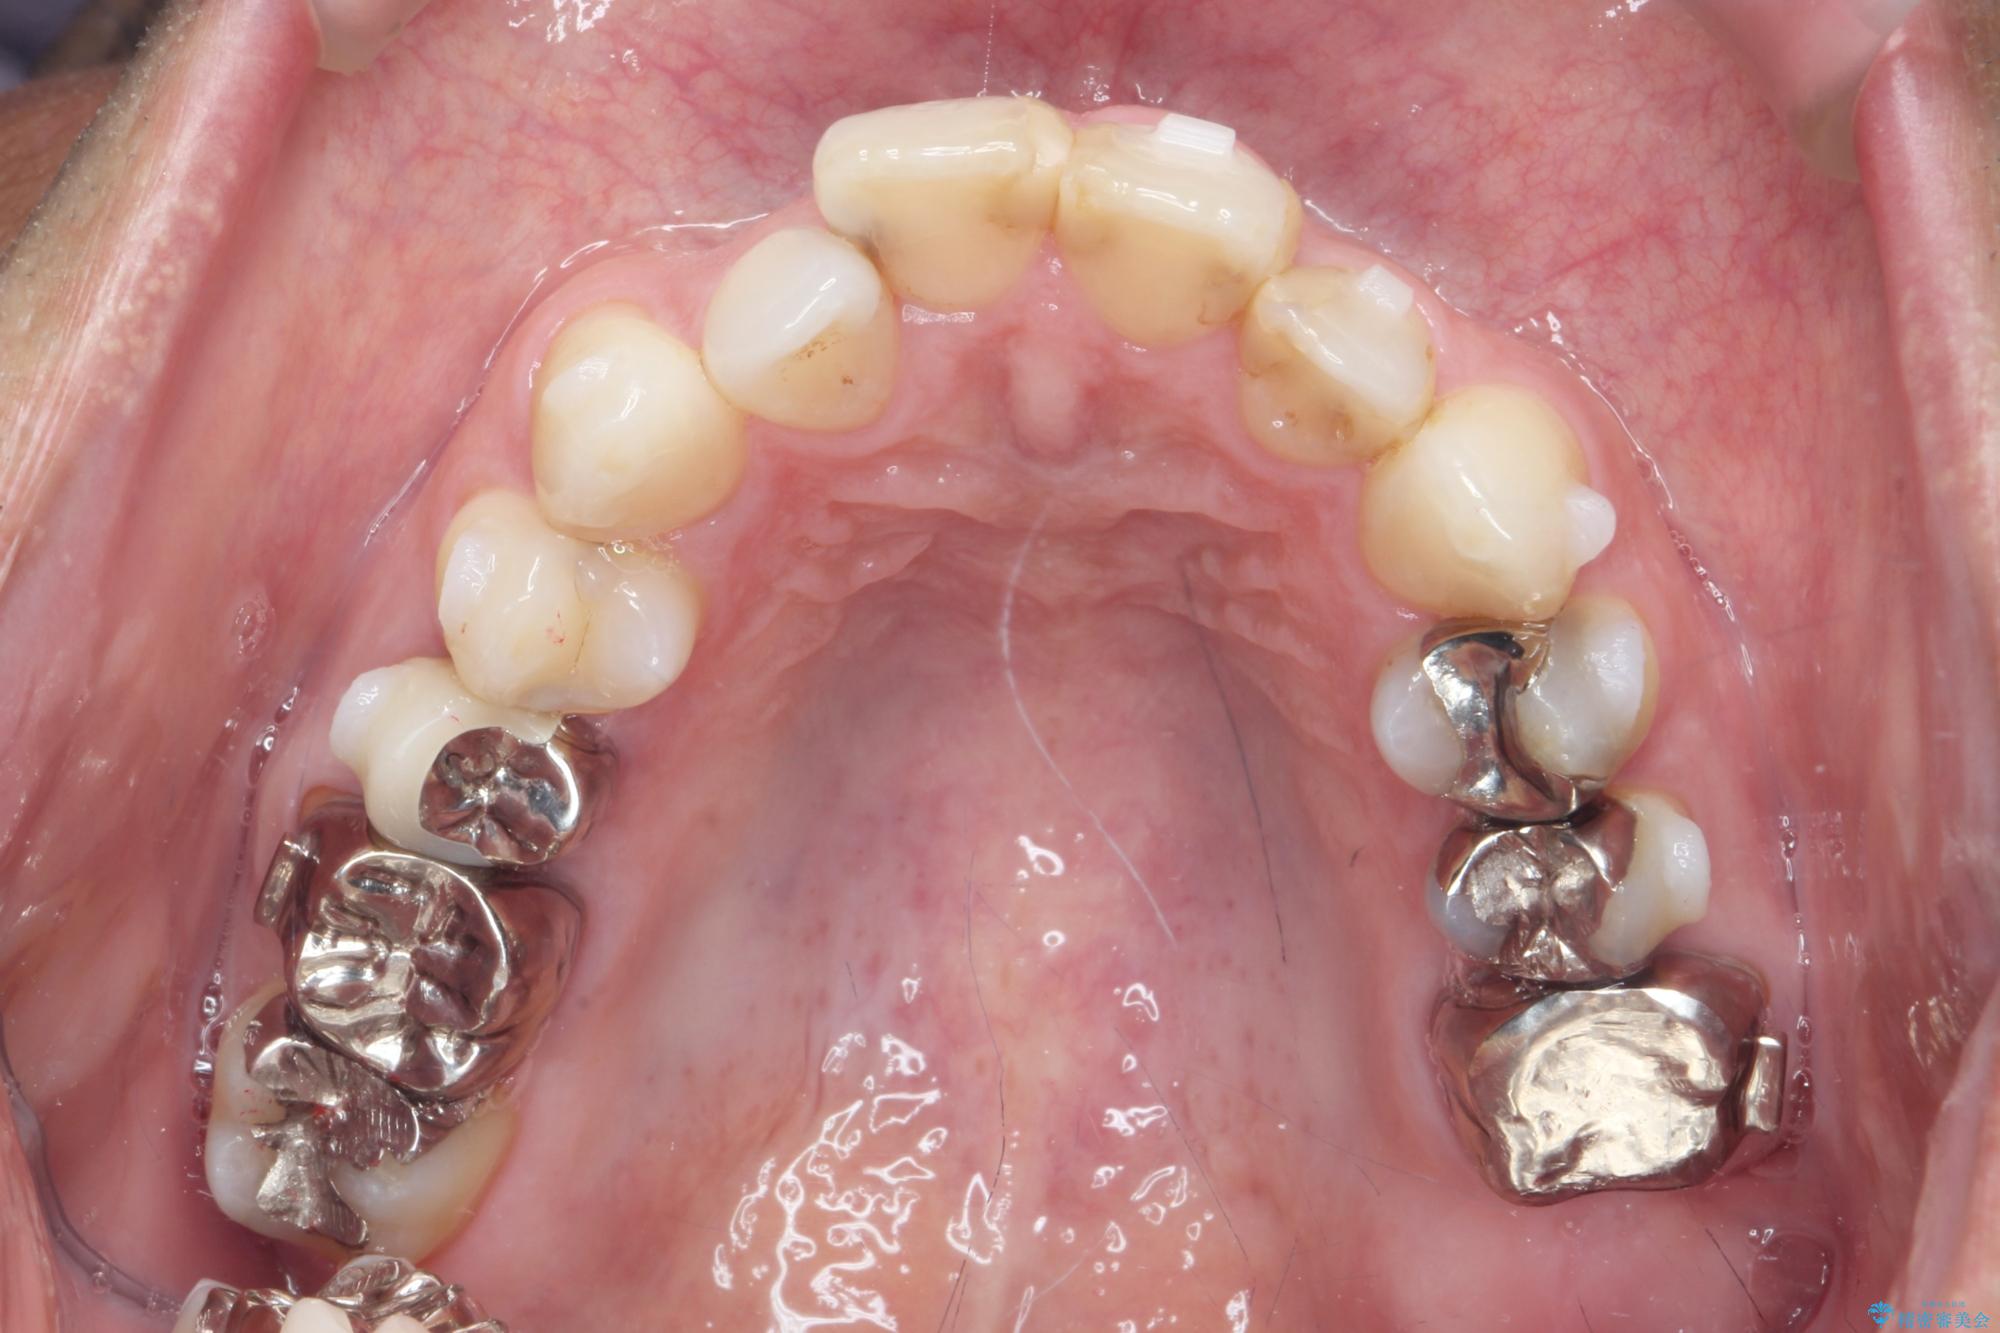

- 突き出た前歯の角度の改善と虫歯治療の改善を求めて来院されました。

虫歯を除去したのち、マウスピース矯正治療を行い、歯並びやがたつきを改善したのち、セラミックに置き換えることで審美性の向上を計画します。